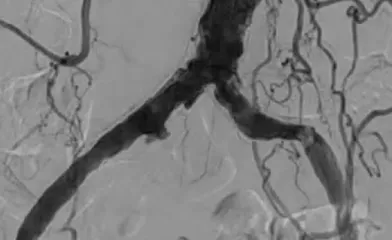

ケースレポート実際の臨床応用を通じて、製品への理解をさらに深めてください。 製品に関連するケースレポートをご覧ください並び替え昇順降順並び替え 昇順降順ポートフォリオ大動脈領域末梢血管領域ポートフォリオ 大動脈領域末梢血管領域関連製品ゴア® TAG® コンフォーマブル 胸部大動脈ステントグラフト アクティブコントロールシステムゴア® エクスクルーダー® IBEゴア® エクスクルーダー® コンフォーマブル AAAステントグラフト アクティブコントロールシステムゴア® バイアバーン® VBX バルーン拡張型ステントグラフト ゴア® バイアバーン® ステントグラフト関連製品 ゴア® TAG® コンフォーマブル 胸部大動脈ステントグラフト アクティブコントロールシステムゴア® エクスクルーダー® IBEゴア® エクスクルーダー® コンフォーマブル AAAステントグラフト アクティブコントロールシステムゴア® バイアバーン® VBX バルーン拡張型ステントグラフト ゴア® バイアバーン® ステントグラフト治療領域末期腎不全末梢血管疾患胸部大動脈疾患腹部大動脈瘤血管損傷治療領域 末期腎不全末梢血管疾患胸部大動脈疾患腹部大動脈瘤血管損傷 34 結果 Image 6 Fr 対応ゴア® バイアバーン® VBXバルーン拡張型ステントグラフトを用いた橈骨動脈アプローチによる腸骨動脈 EVTの一例 さらに詳しくImage AVGの人工血管延長術後に生じた再流出路狭窄症例に対してゴア® バイアバーン® ステントグラフトを挿入した一例 さらに詳しくImage DESによる左浅大腿動脈の慢性閉塞の治療後、コロナ禍の受診中断でステント内閉塞となり再来された一例 さらに詳しくImage SFAの長区域閉塞病変にゴア® バイアバーン® ステントグラフトを留置し、3年フォローした一例 さらに詳しくImage SFA入口部からの長区間超高度石灰化閉塞病変に対して外科的内膜摘除術との併用でゴア®バイアバーン® ステントグラフトを留置し、6か月フォローした一例 さらに詳しくImage SFA起始部のランディングに悩むCTO病変に対しゴア® バイアバーン® ステントグラフトを用いてEVTを完遂し、2年経過を観察した一例 さらに詳しくImage Shaggy Aortaを合併した遠位弓部大動脈瘤に対するTEVAR さらに詳しくImage ケースレポート:ゴア® TAG® コンフォーマブル 胸部大動脈ステントグラフト アクティブコントロールシステム さらに詳しくImage ケースレポート:ゴア® エクスクルーダー® IBE さらに詳しくImage ケースレポート:ゴア® バイアバーン® VBX バルーン拡張型ステントグラフト さらに詳しくImage ケースレポート:ゴア® バイアバーン® ステントグラフト さらに詳しくImage ケースレポート:外傷性胸部大動脈損傷に対するゴア® TAG® コンフォーマブル 胸部大動脈ステントグラフト アクティブコントロールシステムの有用性 さらに詳しくImage ゴア® TAG® コンフォーマブル 胸部大動脈ステントグラフト アクティブコントロールシステムの特徴および有用性 さらに詳しくImage ゴア® バイアバーン® ステントグラフトの使い所 –長期開存したISO症例– さらに詳しくImage ゴア® バイアバーン® ステントグラフトを人工血管内シャント静脈側吻合部狭窄のリコイルに対して用いた症例 さらに詳しく さらに表示 トップ